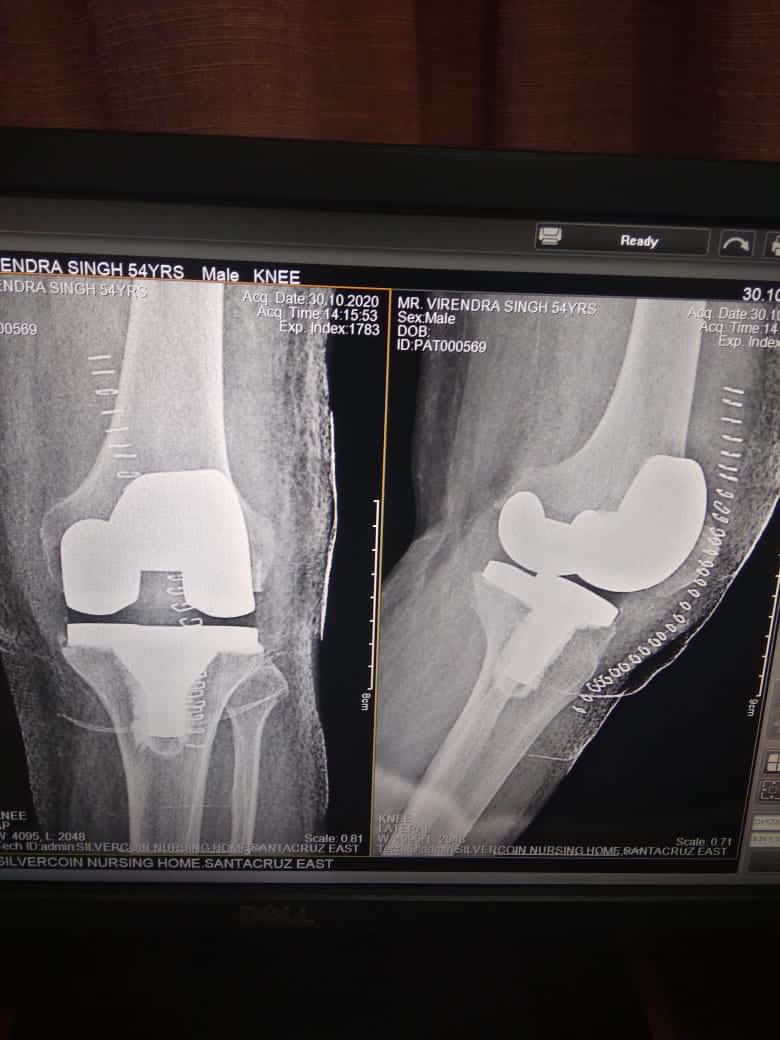

Best KNEE REPLACEMENT SURGEON IN ANDHERI